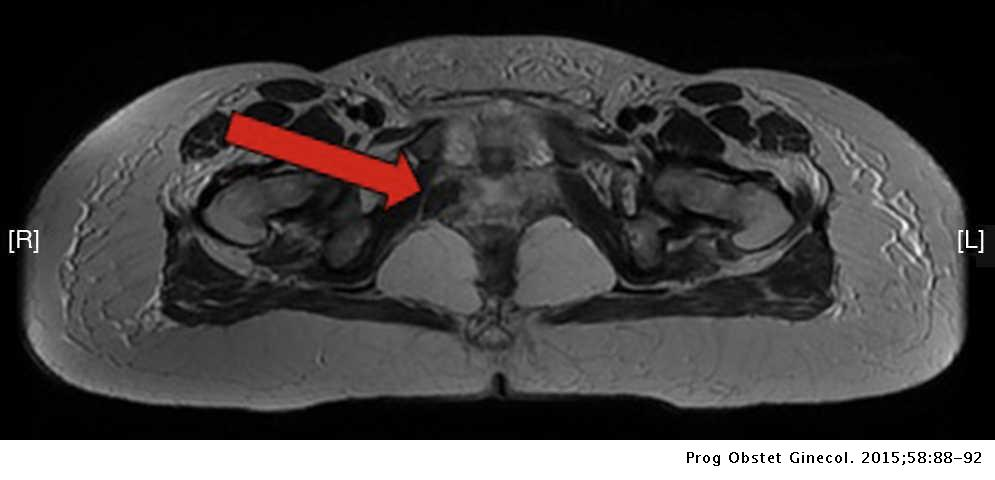

Las pruebas de resonancia magnética y de latencia del nervio pudendo, son de utilidad en algnos casos.